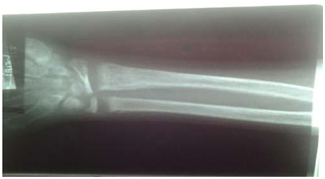

The X‐ray of the wrist as shown in Figure 3 showed cupping and fraying of metaphyseal regions.

Figure 3 X‐ray of the wrist and arm.